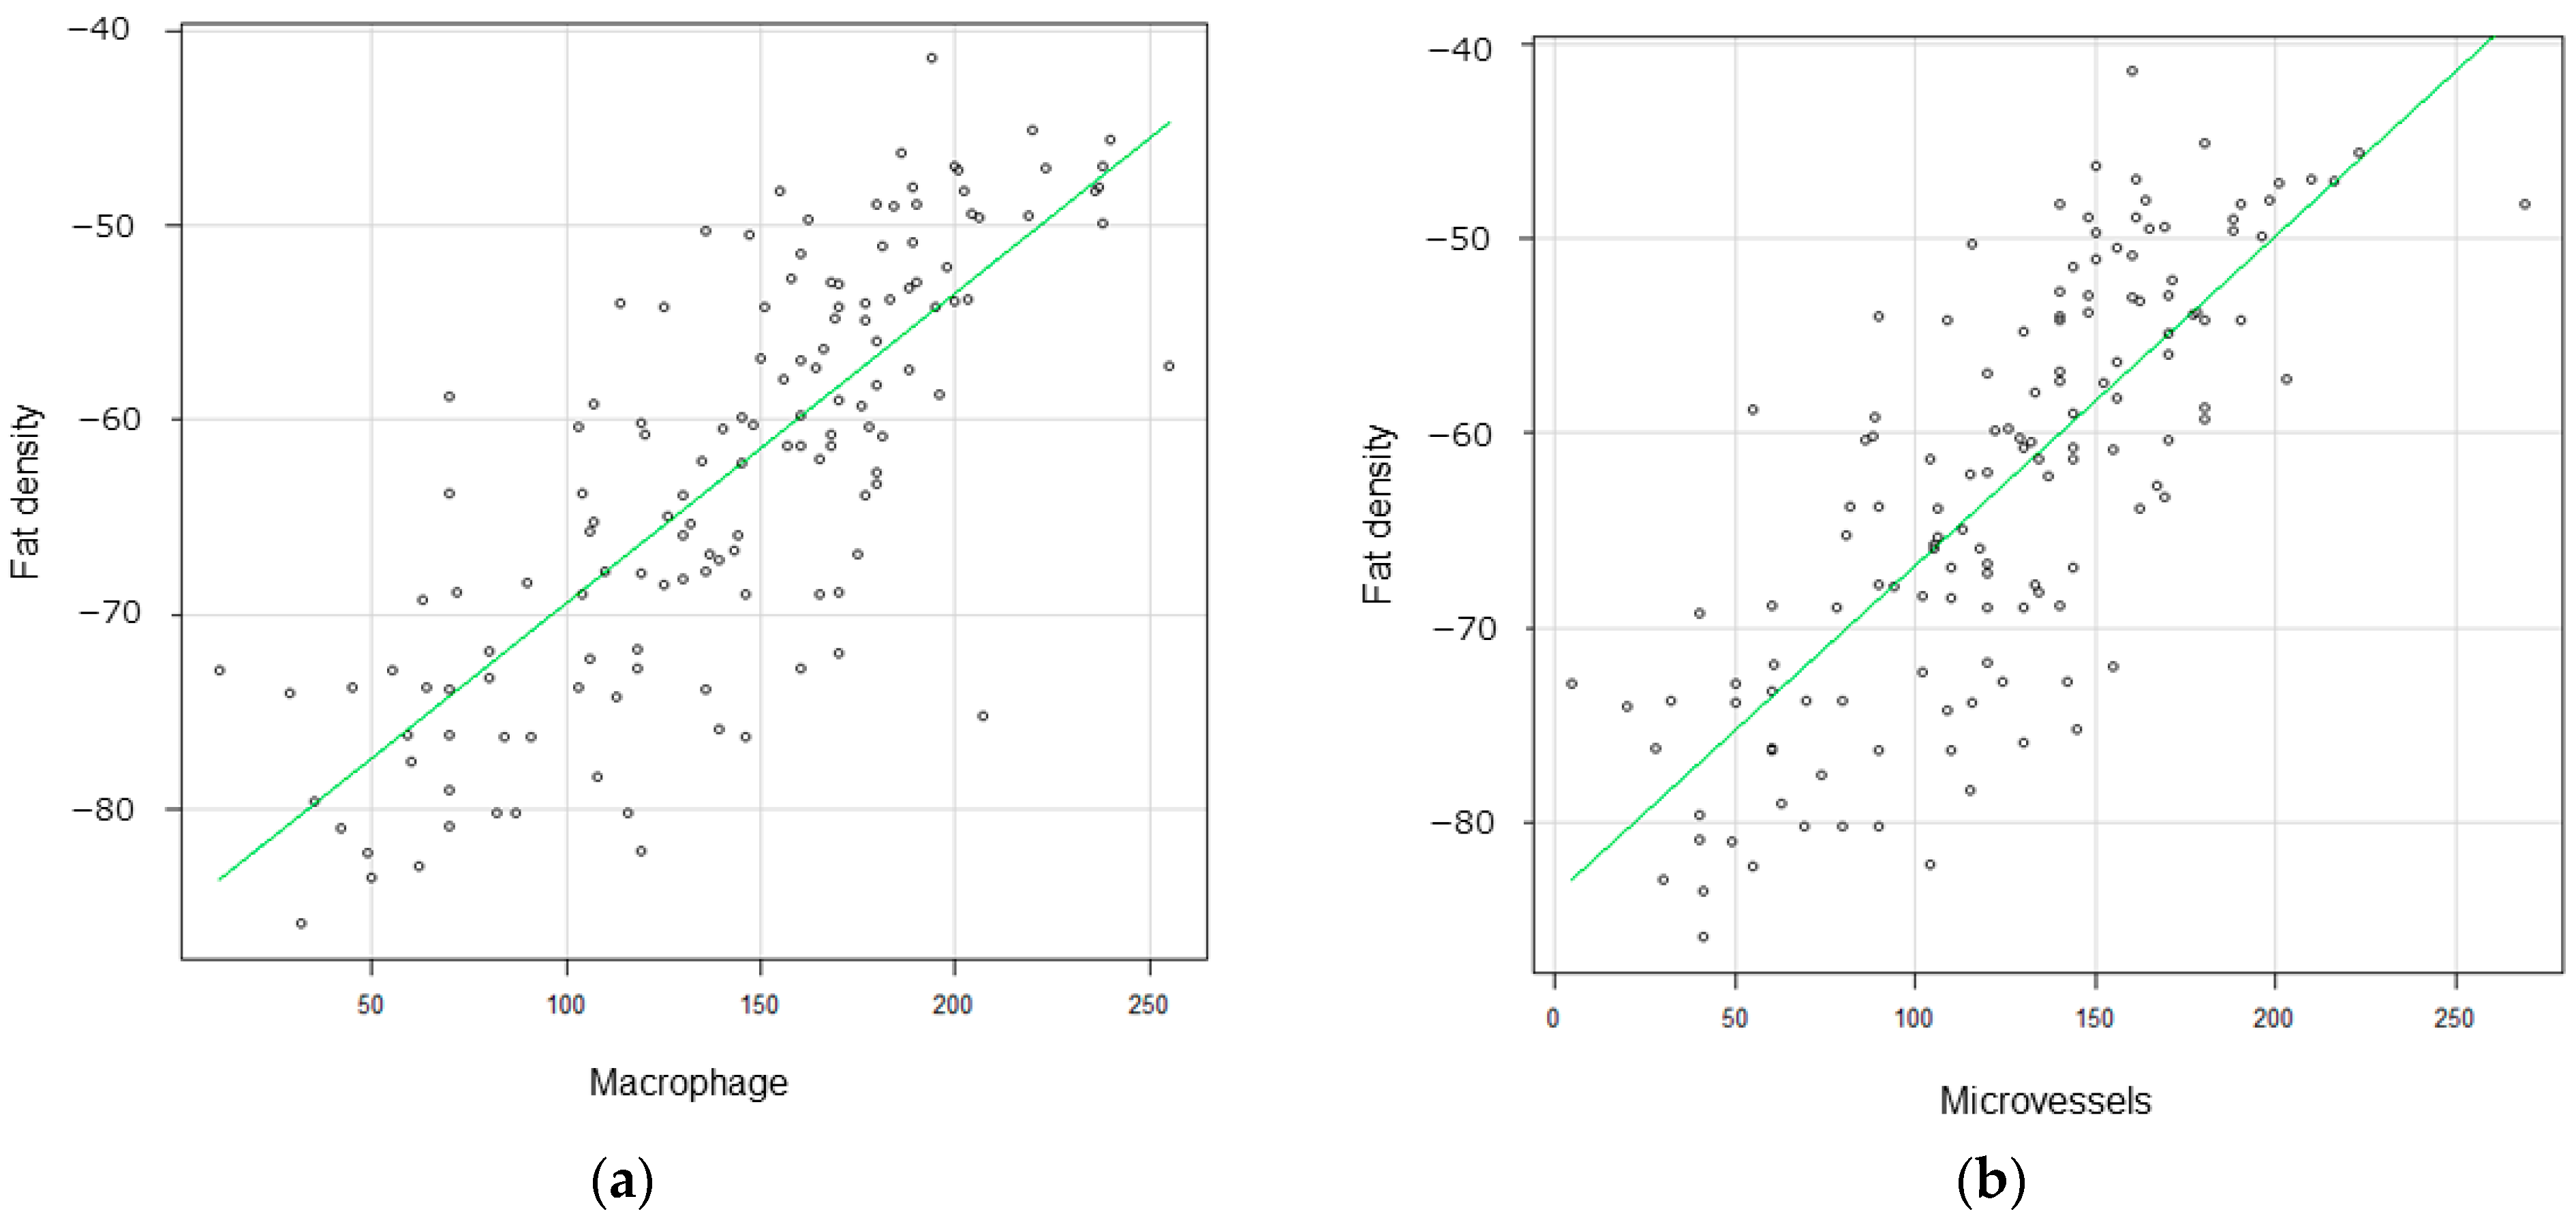

3.3. Correlation between Pericarotid Fat Density and IHC